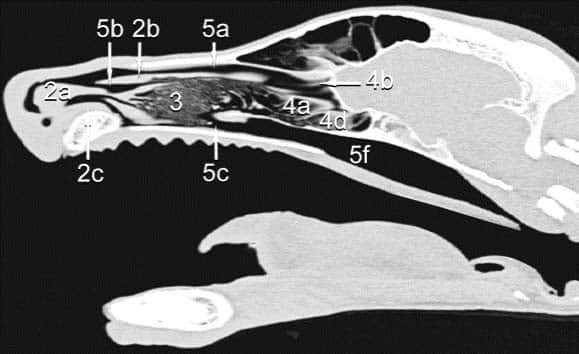

Die Beschwerden kurznasiger Hunde können bei warmen Umgebungstemperaturen dramatisch zunehmen und zum Kollaps führen. Die Ursache für die extreme Wärmeempfindlichkeit ist weniger eine unzureichende Belüftung der Lunge und damit eine Störung des Gasaustausches, sondern die unzureichende Nasenatmung dieser Tiere. Im Gegensatz zum Menschen braucht der Hund für die Regulation seines Wärmehaushalts unverzichtbar eine »funktionierende« Nase: Wenn es draußen heiß ist, beginnt der Mensch zu schwitzen. Dabei wird das Wasser der Schweißdrüsen auf der großen Oberfläche der Haut verteilt und verdunstet. So entsteht die »Verdunstungskälte«, die das Blut in der Haut herunterkühlt. Hunde können nicht schwitzen wie der Mensch, sie haben kaum Schweißdrüsen, Hunde hecheln. Aber auch sie nutzen das Prinzip der Verdunstungskälte. Sie haben ihre große Oberfläche innerhalb der Nase: ein anatomisches Wunderwerk von feinsten Nasenmuscheln (Abb. 1, Nr. 3). Durch diese Muscheln strömt auch beim Hecheln die Einatemluft und erzeugt auf der durch Drüsen befeuchteten Oberfläche die Verdunstungskälte. Brachyzephale Tiere haben derart verkleinerte und kaum belüftete Nasenmuscheln, dass die Thermoregulation nicht mehr funktionieren kann. Deswegen sind brachyzephale Tiere besonders wärmeempfindlich, oft bereits bei Temperaturen ab 19°C und nach Belastung dauert die Erholungszeit viele Stunden [3].